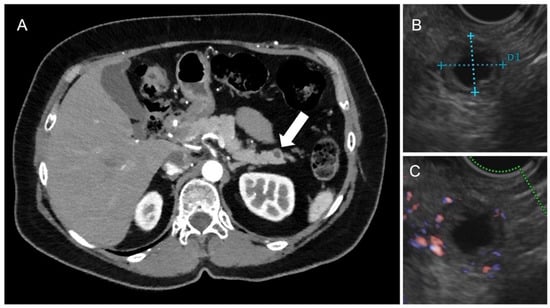

3.1. Pancreatic NENs